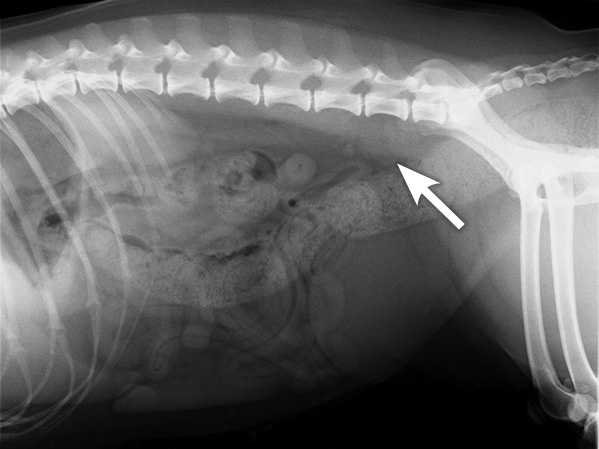

X-ray of a patient with mildly enlarged lymph nodes under the spine (arrow)